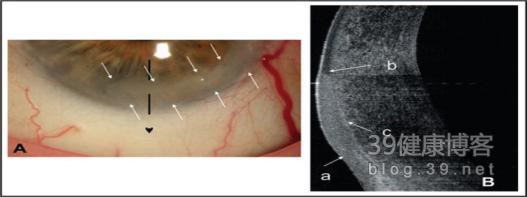

图20 早期角膜上皮内上皮癌病变(2)。(A)裂隙灯照片显示下方结膜、角膜上皮内病变(结膜和角膜上皮内原位癌,白色箭头)。黑色箭头表示OCT成像的位置。(b)OCT图像显示高反光的上皮层增厚(a)、鲍曼氏层(b)和突然过渡的上皮细胞(c)。